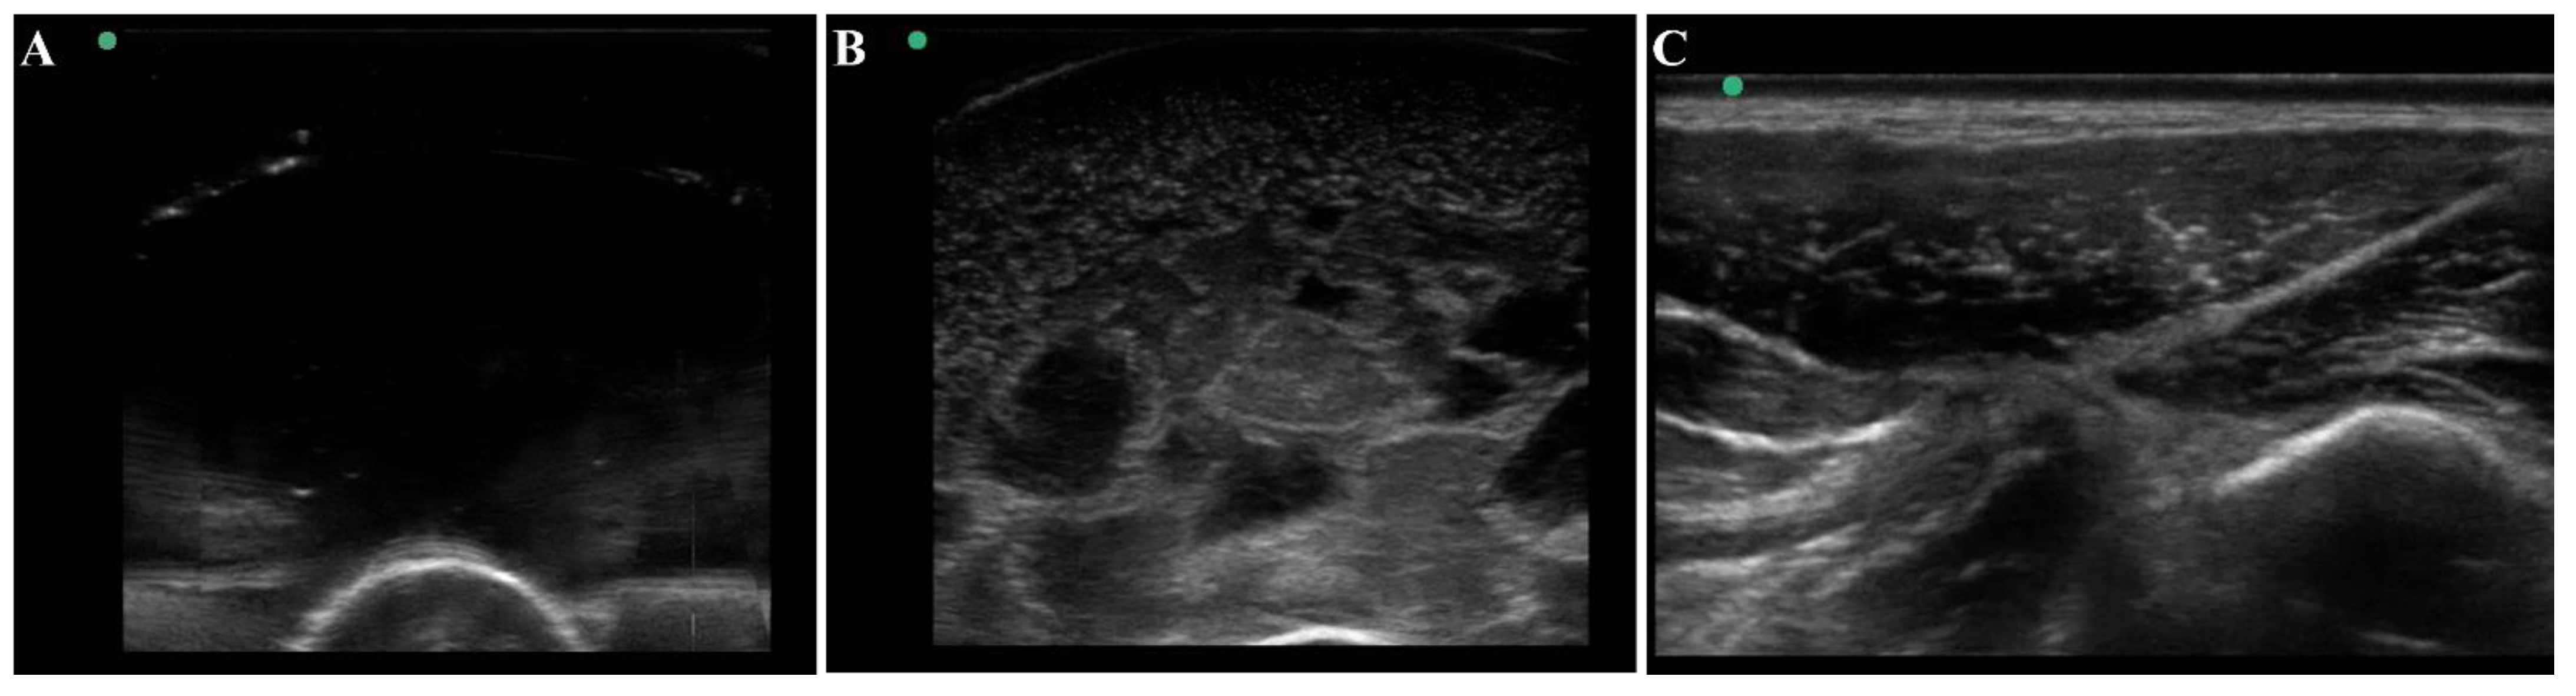

3.1. Overview of the Tissue Phantom for Shrapnel Image Acquisition

2.3. Ultrasound Shrapnel Imaging